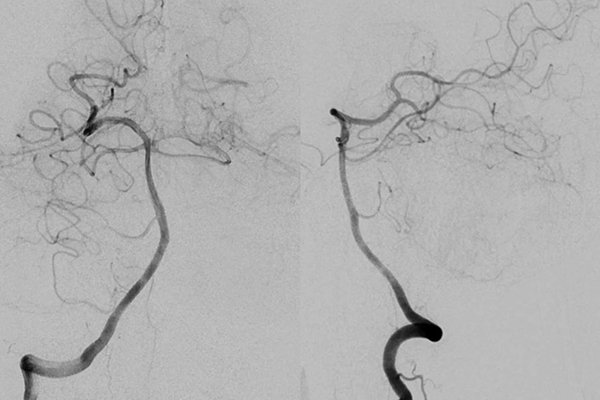

【垂医病例科普】神经外科:少见的中脑周…